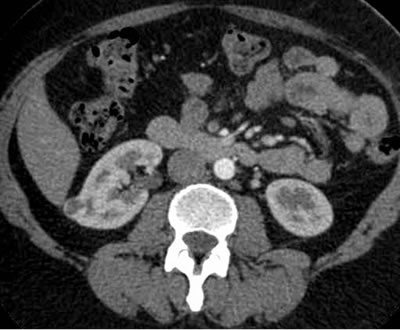

КТ (Компьютерная томография)

КТ (Компьютерная томография). Рак почки.